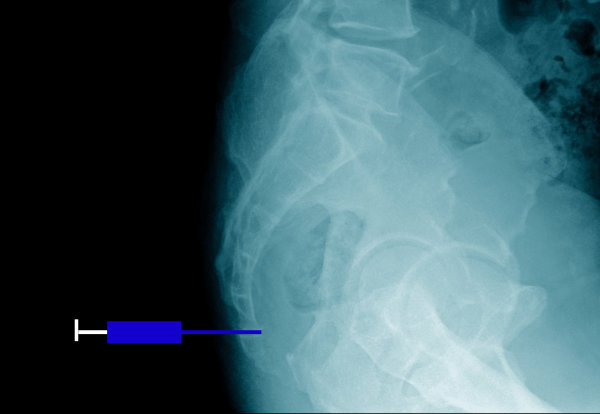

- Zwykłe zdjęcie rentgenowskie wykonujemy po upadku, aby stwierdzić czy jest to tylko stłuczenie, czy też złamanie kości ogonowej. To badanie pozwala również na ocenę budowy kości guzicznej, gdyż odstająca lub krzywa kość ogonowa może przyczyniać się do powstania bólu.

- W przypadku przewlekłych dolegliwości można wykonać RTG czynnościowe, które obrazuje kość ogonową podczas stania oraz siedzenia. Porównanie tych obrazów umożliwia znalezienie nadmiernej lub zmniejszonej ruchomości kości guzicznej, które mogą być przyczynami bólu.

- Rezonans magnetyczny lub/i tomografia komputerowa są rzadko potrzebne. Stosujemy te badania, kiedy zachodzi potrzeba uzyskania bardzo dokładnych obrazów. Ma to szczególne znaczenie w przy podejrzeniu złamania lub guza kości guzicznej.